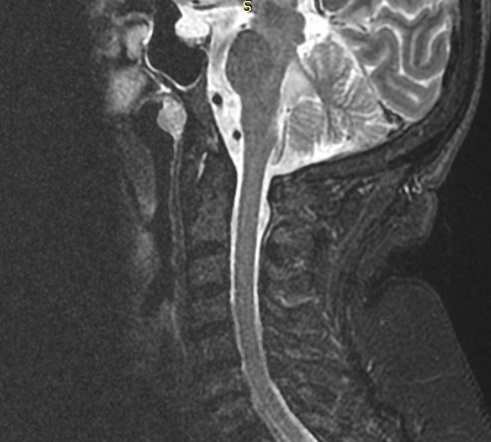

Computed tomography (CT) with sagittal reconstruction of the atlantoaxial joint was also performed showing no erosions nor destructive lesions of the odontoid cortical bone. There were an anterior atlanto-dental interval of 5.6 mm (indicating early instability) and a posterior atlanto-dental interval (PADI) of 13.4 mm; notably a PADI <14 mm is a sensitive method of predicting cord compression and a reliable method to identifying high risk patients who should be further assessed with MRI [13,14]. Degenerative disk disease from C5 to C7 was also visualized (Figure 2). A comprehensive clinical and serological evaluation ruled out infections or neoplastic disease.

Figure 2: CT scan of the cervical spine with sagittal multiplanar reconstruction. Atlanto-dental distances: anterior atlanto-dental interval, red line is 5.64 mm (normal <3 mm) indicating atlo-axial early instability and implying transverse ligament damage. Posterior atlanto-dental interval (PADI), green line is 1.34 cm. PADI <1.4 cm is a sensitive method of predicting cord compression